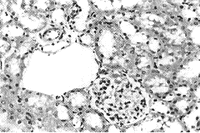

2.5 肾组织光镜下形态学改变 与1组、2组相比,3组、5组近曲小管上皮细胞普遍呈浊肿及水泡变性,可见肾小管坏死,皮质区尤为明显,胞质内胆色素颗粒沉积明显增多,管腔内可见脱落的坏死细胞;集合管内蛋白管型增多,并见细胞管型,部分肾小球凝集,肾小囊间隙增大,间质内有大量淋巴细胞浸润,而4组改变则较3、5组为轻(见图2、3、4、5、6)。

图3 2组大鼠肾组织HE染色病理照片(×40)

Figure 3 The kidney of the rat from group 2 HE×40

图4 3组大鼠肾组织HE染色病理照片(×40)

Figure 4 The kidney of the rat from group 3 HE×40